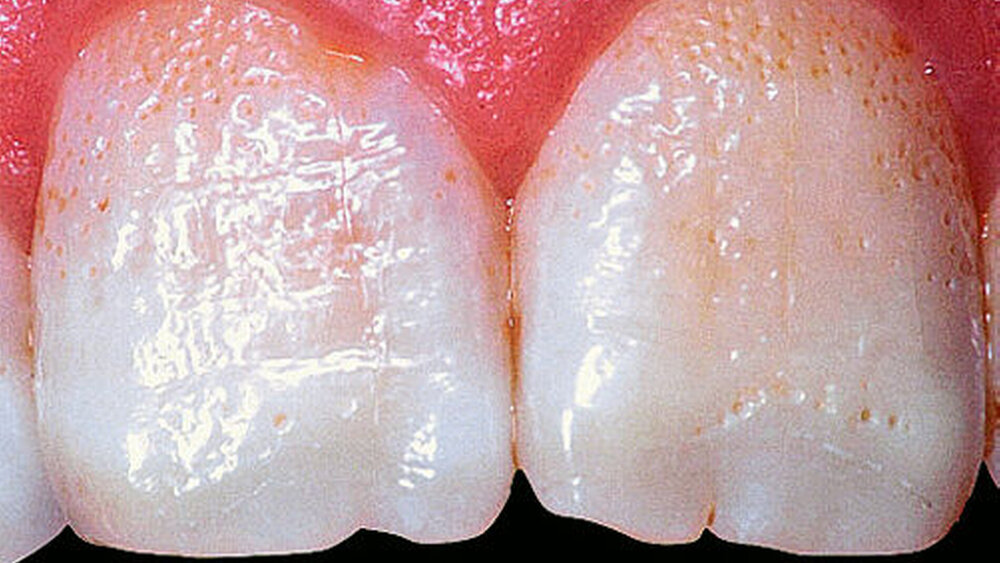

Bei dieser genetisch bedingten Schmelzdysplasie sind in der Regel alle Zähne einer oder beider Dentitionen betroffen, und es ist ein bilateralsymmetrisches Erscheinungsbild vorhanden. Die Ausprägung der Schmelzdefekte kann von Zahn zu Zahn und von Generation zu Generation variieren (Abbildungen 1a bis 1c). Die Struktur des Dentins ist nicht verändert. Die Schmelzdefekte treten als Grübchen von unterschiedlicher Größe in mehr oder weniger normal dickem Schmelz in Erscheinung (Abbildung 2a). Durch Einlagerung von Farbstoffen in diese Grübchen können die Schmelzveränderungen ästhetisch störend wirken (Abbildung 2b). Ähnliche grübchenartige Schmelzhypoplasien können bei Patienten mit Rachitis, Pseudohypoparathyroidismus oder Epidermolysis bullosa beobachtet werden. Bei der hypoplastischen Form der Amelogenesis imperfecta ist die Schmelzhärte normal, die Schmelzdicke jedoch reduziert. Der grübchenartige Typ weist als Ausnahme eine fast normale Schmelzdicke auf (Abbildungen 3 und 4).